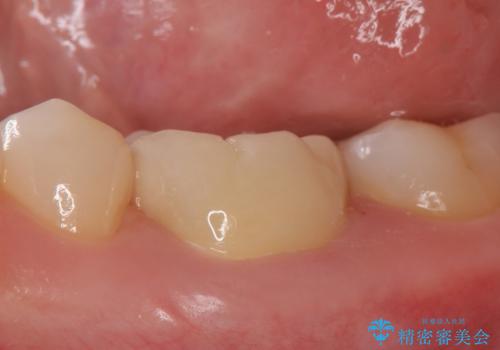

顕微鏡下で精密根管治療を行い、症状の緩解を確認後、オールセラミッククラウンによる補綴を行いました。

- オールセラミッククラウン…¥100,000、仮歯…¥10,000、ファイバーコア…¥20,000費用は治療当時の料金となります

今回用いたオールセラミッククラウンはジルコニアフレームという白い素材の上にセラミックを盛っているため、審美性が非常に高いのが特徴です。

また、ジルコニアは人工ダイヤモンドの材料にも使われているほど高い強度を持っており、そのためオールセラミッククラウンは審美性だけでなく、奥歯やブリッジの補綴も可能とするクラウンです。